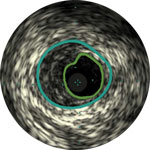

Treatment plan example 1

Lumen

Eccentric fibrotic plaque with deep calcium nodule

Acoustic shadowing

Vessel size: 5.5 mm diameter Plaque morphology: Fibrotic plaque with intimal and medial calcium Plaque geometry: Eccentric lesion Guidewire position: True lumen

Quick-Cross catheter: Confidently cross challenging morphologies Phoenix deflecting atherectomy: Front facing to cut, capture and clear mixed morphologies, including calcium; deflecting capabilities for larger luminal gain AngioSculpt scoring balloon: Score calcium to reduce dissection4 Stellarex DCB: Designed for performance in calcium